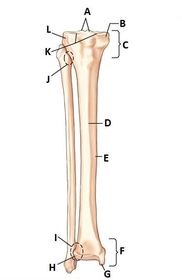

A. medial condyle (tibia) B. tibia body C. medial malleolus D. lateral malleolus E. fibula body F. neck fibula G. head fibula H. apex fibula I. lateral condyle tibia J. intercondylar eminence